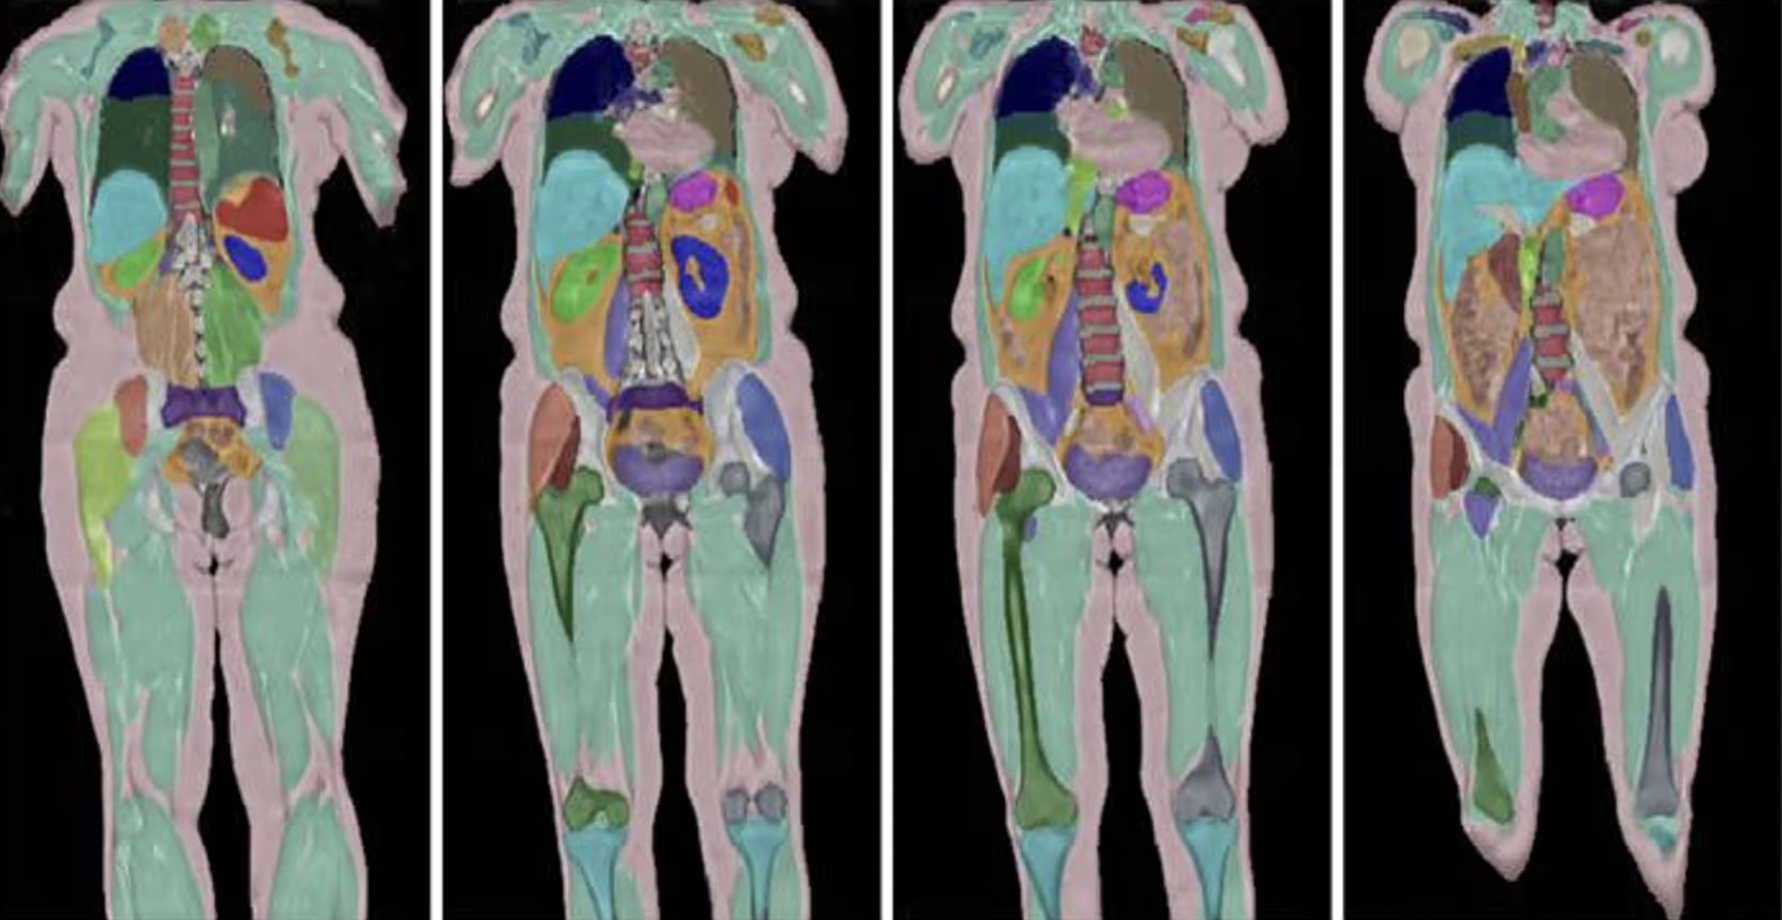

UK Biobank завершил многолетний проект по полному МРТ-сканированию 100 тысяч добровольцев. Полученные более миллиарда обезличенных изображений теперь доступны ученым по всему миру. Они охватывают мозг, сердце, кости, сосуды и внутренние органы участников, а также сопровождаются медицинской историей, генетическими данными и информацией о здоровье и образе жизни. Об этом пишет The Guardian.

Исследование показало, что два человека с одинаковым индексом массы тела и окружностью талии могут иметь разное распределение жира. Сканирование позволяет оценить объем висцерального жира — жировой ткани вокруг внутренних органов, которая напрямую влияет на риск сердечно-сосудистых заболеваний и диабета.

UK Biobank начал повторное сканирование 60 тысяч участников, чтобы зафиксировать, как со временем меняется тело человека. По словам профессора Луизы Томас, сравнение сканов, сделанных с интервалом в два года, выявило увеличение висцерального жира и жировое перерождение мышц: «С возрастом наши тела становятся всё более мраморными. Мы буквально превращаемся в вагю».